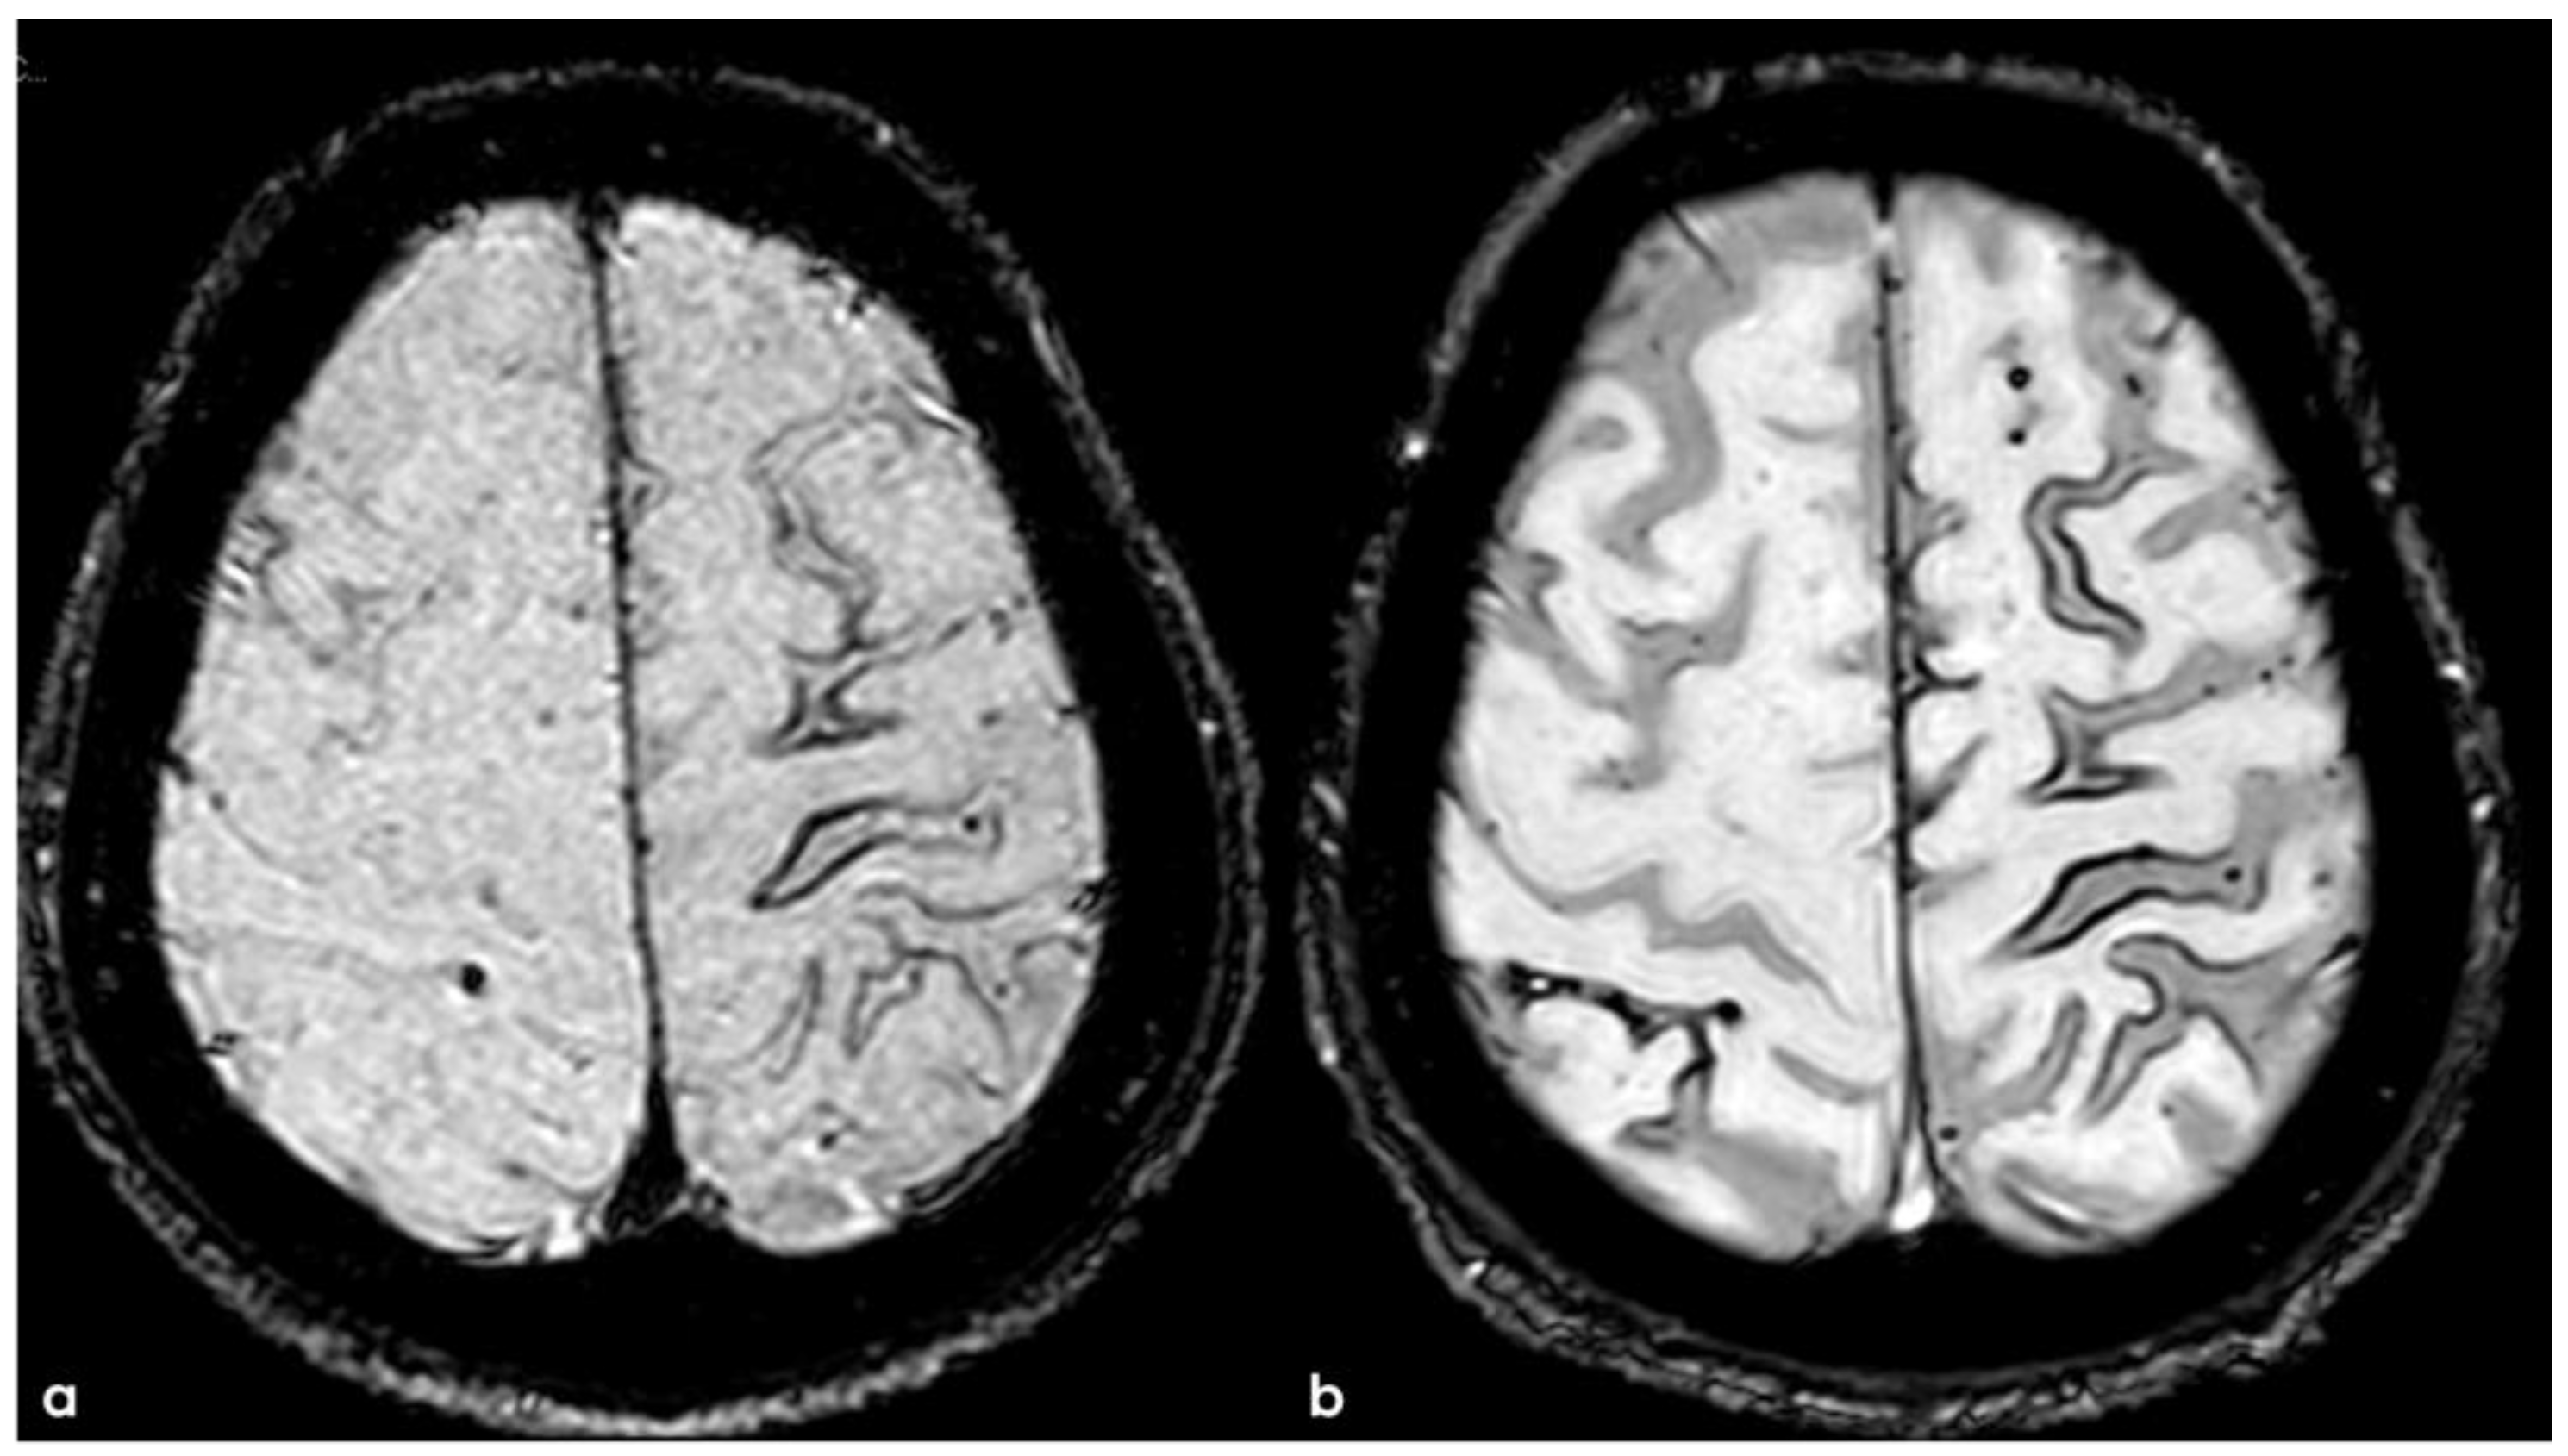

3. May 2014: CAA-Related Inflammation